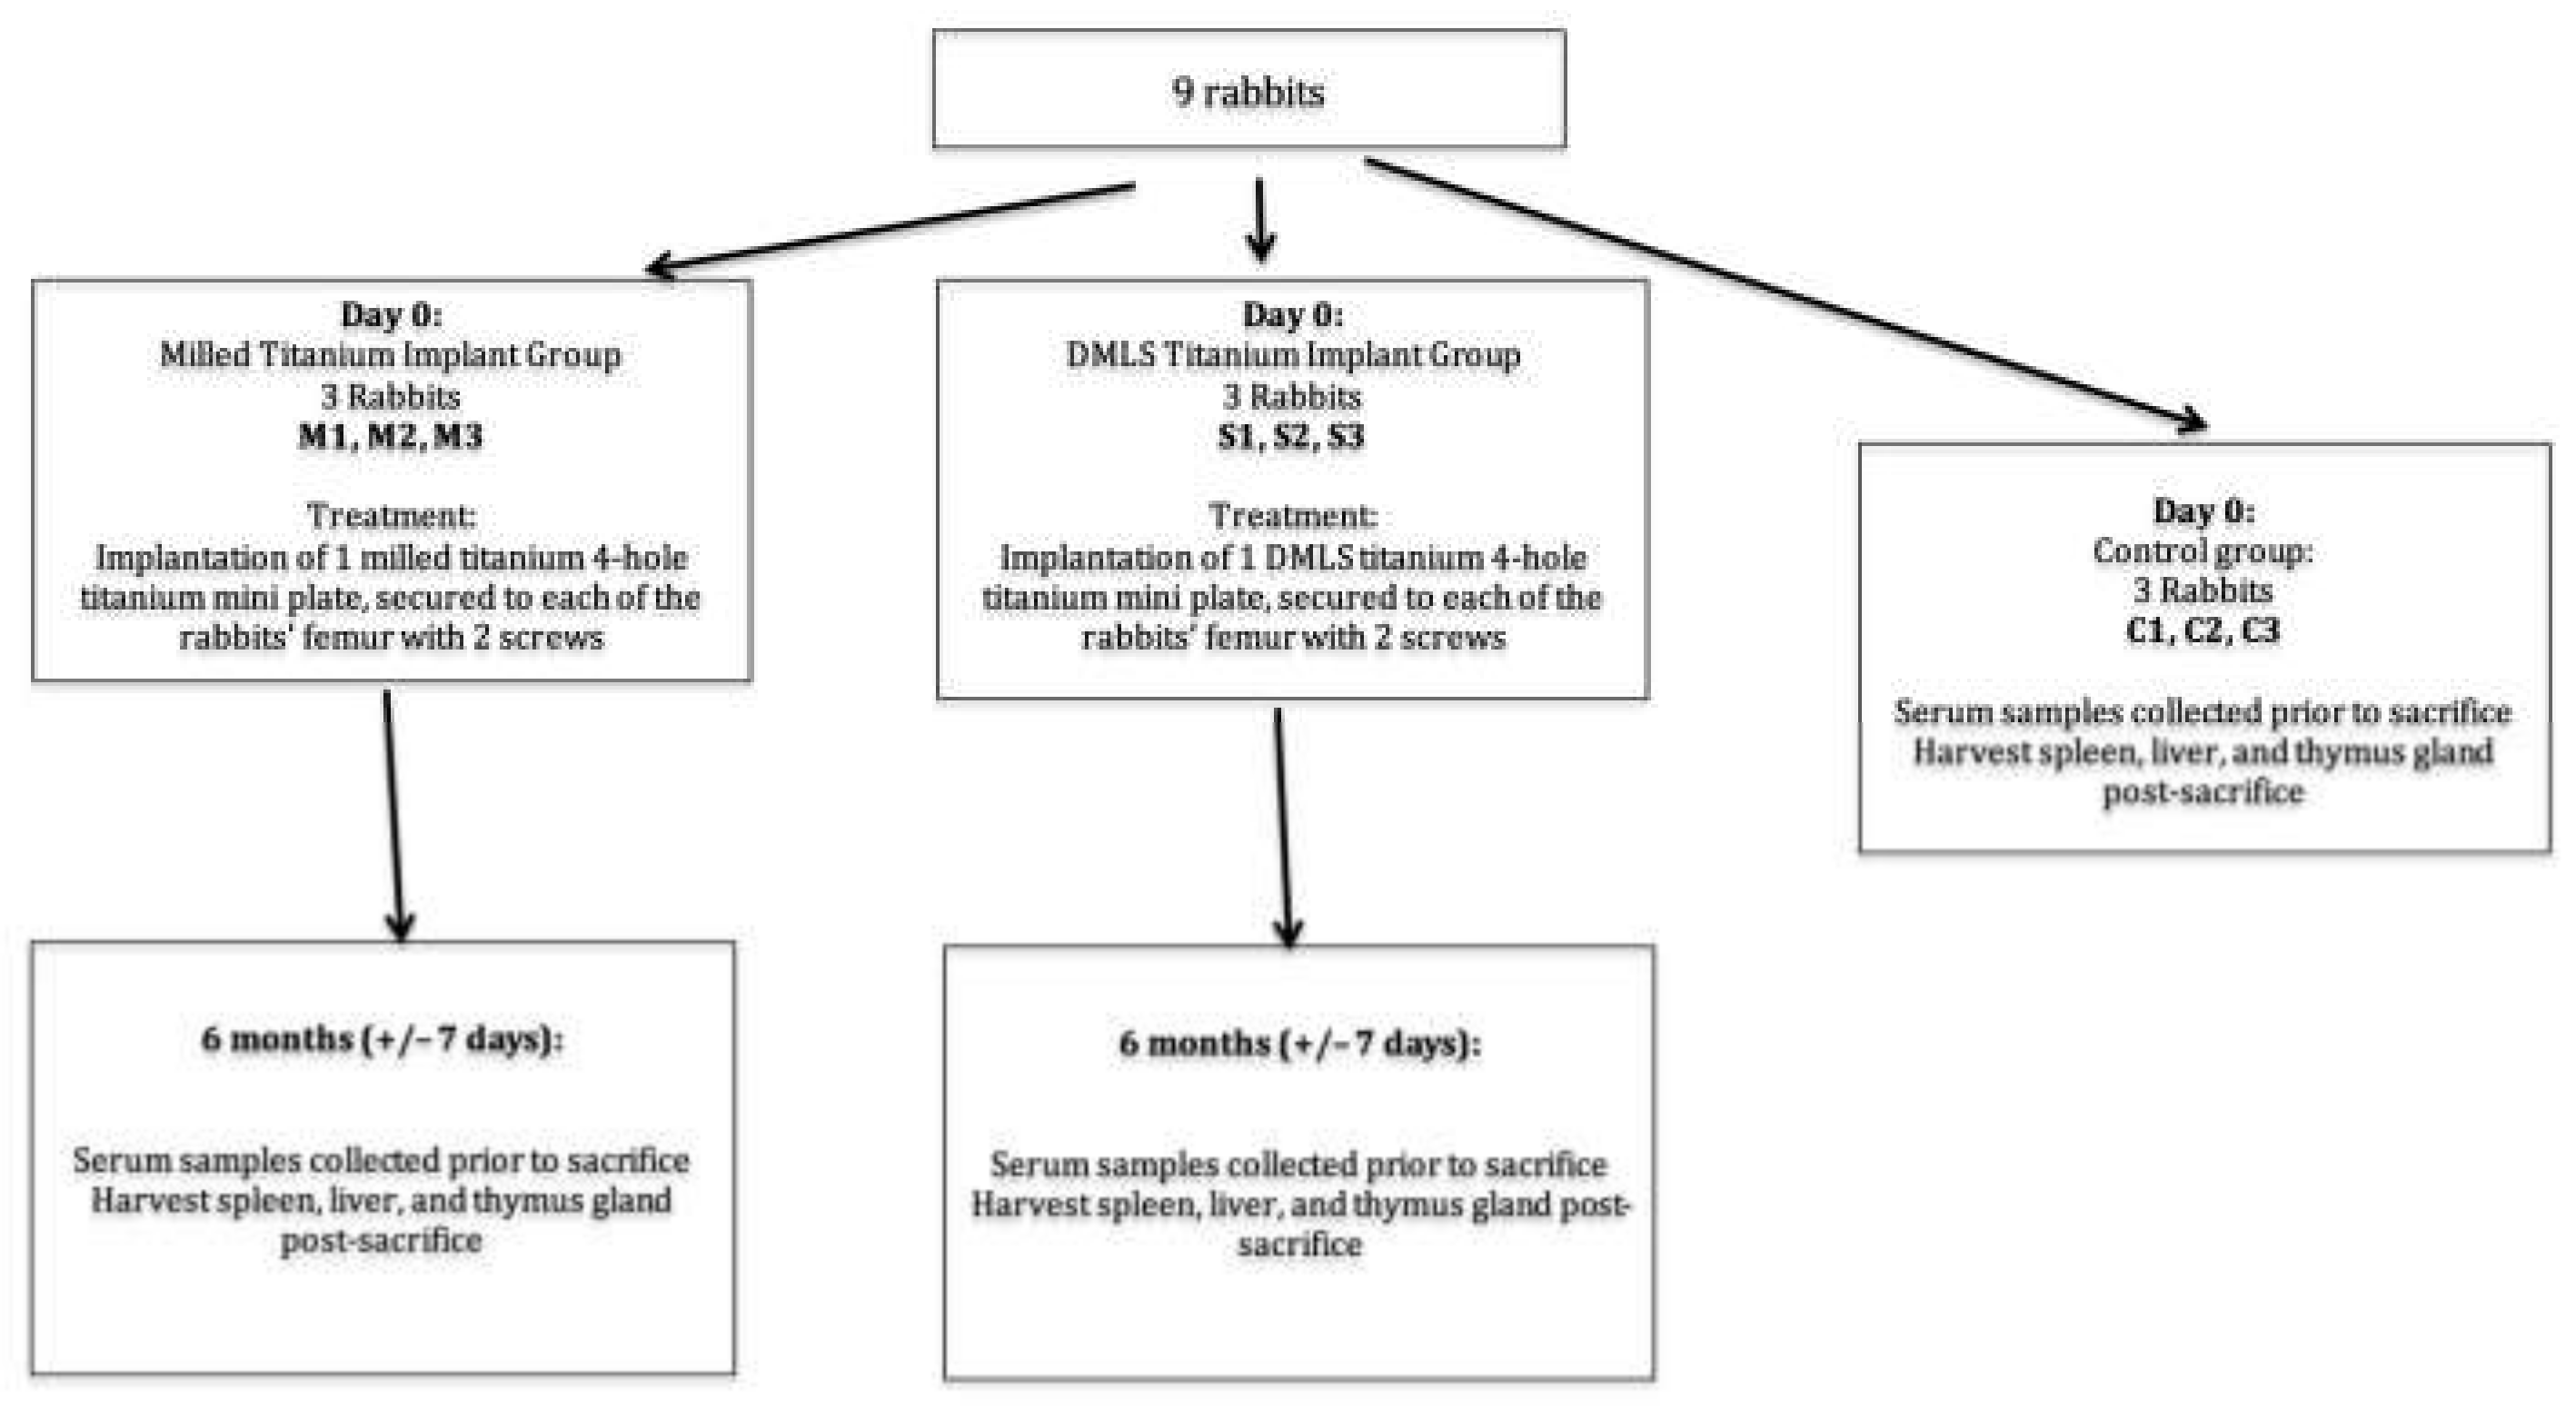

4.2. Experimental Animals

4.2.1. Animal Group and Study Design

4.2.2. Implantation of Titanium Plates and Screws

4.2.3. Blood-Sample Collection for Serum-Titanium Analysis

4.2.4. Sacrifice of Animals and Harvesting Lymph-Reticular Organ Tissues (for Organ-Titanium Analysis)